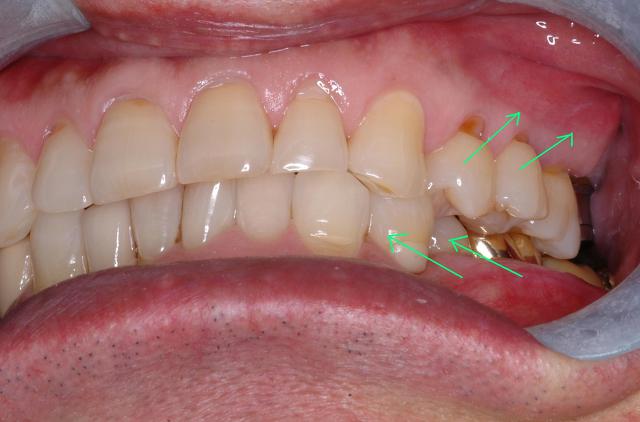

환자의 왼쪽 부위 사진으로 문제의 원인을 보여줍니다.

왼쪽 위 작은 어금니를 바깥으로

왼쪽 아래 작은 어금니는 안으로 누워있습니다.

이렇게 되면 아래턱의 전후적, 수직적 위치가 이상적인(정상적인) 위치에서 벗어나게 됩니다.

그에 따라 턱운동의 불안정성이 야기 됩니다.

환자분의 입을 벌리고 닫는 속도가 느립니다.

기울어져서 씹히고 있는 왼쪽 작은 어금니들은

치아 장축(long axis)으로 힘을 받지 못해

치경부(치아의 옆구리)가 패이는 현상을 나타나게 됩니다.